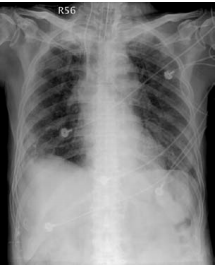

3. 82歲老婦人到院主訴五天來有日趨嚴重的呼吸困難。病史顯示30年前就有醫師告知心臟雜音,因無症狀,未曾有任何治療。近五年來運動耐受逐漸不佳,且偶有突發性悸動及心絞痛,特別在步行樓梯間更加惡化。住院當日清晨3點突然重度呼吸困難,因而急診住院。理學檢查:血壓110/62 mmHg;心跳90/分;頸靜脈怒張。心臟大小正常,但在右上胸骨緣及心尖部有Gr III/VI systolic murmur, S2減輕:其他所見尚無異常。其胸部X光、心臟超音波及心電圖如圖。WBC,5.2 k/micro L;AST,21U/L;CK,111U/L;CK-MB,14.6U/L;Troponin I,0.06 ng/ml。請問下列何項處置最恰當? (A) Percutaneous coronary intervention (B) Aortic valve replacement (C) Nitroglycerin IV infusion at the rate of 15mcg/min (D) Titrate PO carvedilol starting from 3.125 mg and reassess in 3 months (E) Treating with IV digoxin 0.125mg in conjunction with IV bolus Furosemide 20mg and then 20 mg BID

胸部 X 光